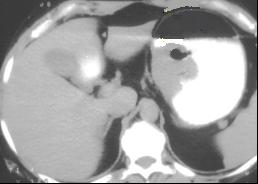

Leiomyome de la face

posterieure de estoma .Image isodense a taillre

marquee , bord reguliere , lisse situe a la face

posteriere de estoma . La paroie de estoma est

normale |